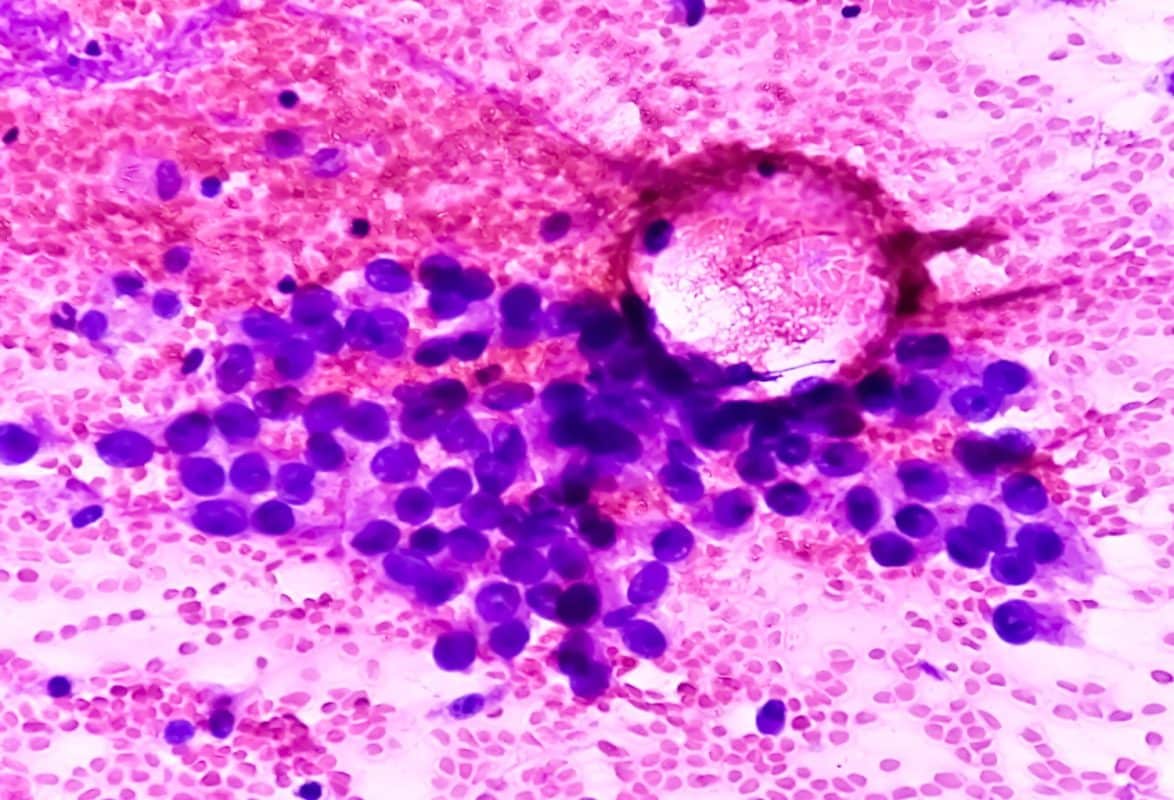

- ביופסיה – נטילת דגימה קטנה מהנגע ושליחתה לבדיקה פתולוגית.